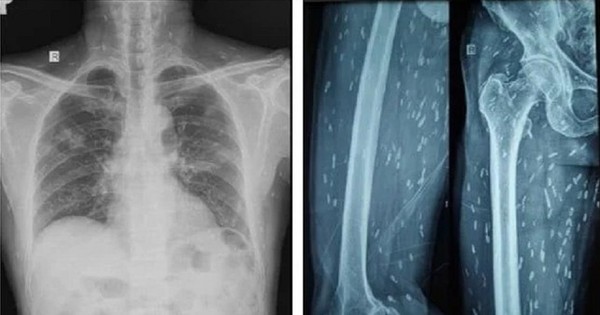

Trên kết quả X-quang và CT-Scan toàn thân, bác sĩ phát hiện bệnh nhân có vô số nang sán dải còn sống hoặc đã bị vôi hóa ở não, nhu mô phổi, trong da, cơ trên toàn bộ cơ thể. Qua điều tra dịch tễ, bác sĩ ghi nhận bệnh nhân có thói quen hay ăn gỏi thịt lợn tái sống và uống nước không đun sôi trong nhiều năm.

Ấu trùng nang sán dải lợn ký sinh khắp cơ thể người bệnh được phát hiện trên kết quả kiểm tra hình ảnh